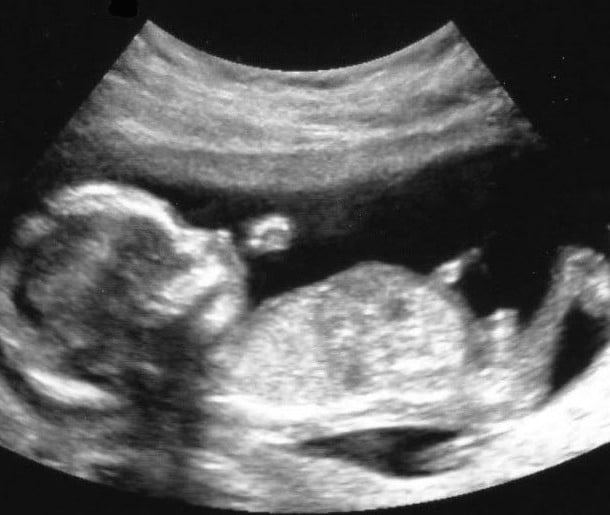

14 haftalık gebelik süreci